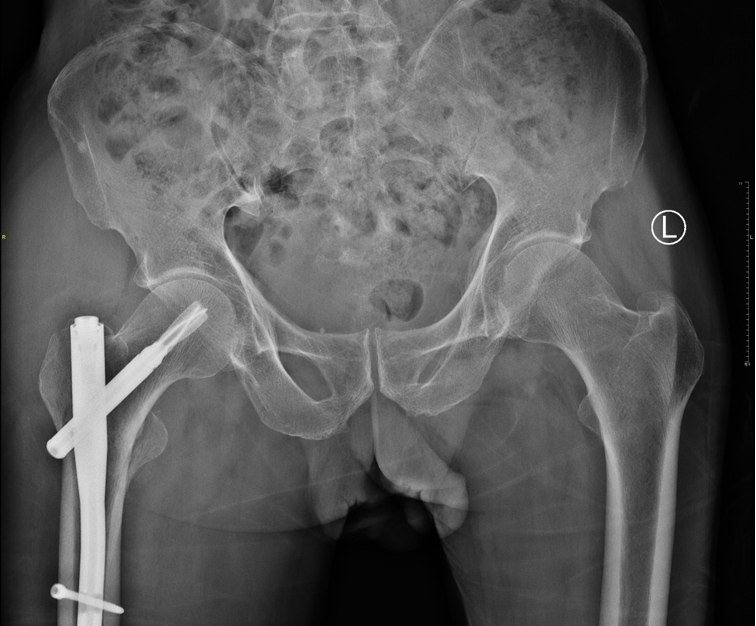

据统计,精品专科建设以来已收治老年髋部骨折患者 114 例,年龄跨度 64 至 90 岁,平均年龄 81.5 岁。其中 106 例接受手术治疗,最快实现 24 小时内手术,快速处理组平均术前等待时间仅 54 小时;8 例采取保守治疗,均得到规范管理。手术全部采用微创闭合复位髓内钉固定术,具有创伤小、出血少、恢复快等优势,患者术后第一天即可床上坐起,第二天便能在医护及家属协助下轻微负重活动。科室还建立完善的质控体系,对围手术期时间、手术质量、术后愈合及住院时长等指标严格把关,患者随访满意度极高。